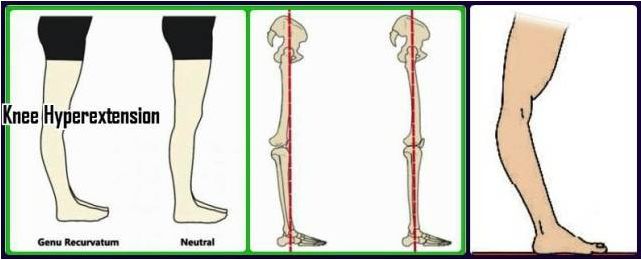

· 膝超伸:膝盖过度 伸展 ,从侧面观察,股骨大转子、股骨外髁和外踝的相对位置,如果股骨外髁位于股骨大转子和外踝连线的后面,则为膝超伸。

生活 、工作中的所有习惯,都是形成各种各样不同体态的非常重要的原因。长期伏案工作的人,容易导致含胸驼背; 长期看电脑的人,容易导致头前探; 长期背重物会加剧含胸驼背探头,甚至造成足弓塌陷; 长期工作穿高跟鞋易导致 盆骨 前倾、膝超伸。这些长期的习惯导致了身体的前后肌肉张力失去平衡,时间久一点,肌肉软 组织 就会拉着骨关节去到不该去的位置,最终使骨关节的排列出现异常,导致我们形成了形态各异的身体姿势。

从生物力学的角度来说,良好的体态下,身体的各个部位:脚、膝盖、骨盆、胸廓和 头部 保持正确的排列,在这种情况下,肌肉的使用将会最小化 。虽然人体的骨骼组织看似僵硬,但是其本质还是动态的,能够承受较大的负荷。可如果在幼年骨骼发育期时身体持续性地、在不正确的体态和身 体位 置上,或长期超出成长位置的时候就会发生骨骼变异,比如 X 型腿,这种情况往往都是不可逆的。